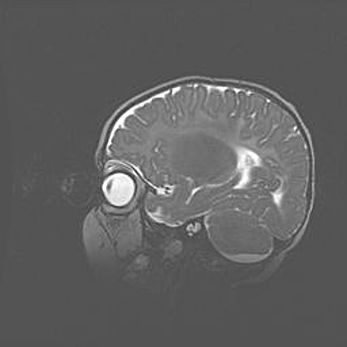

Аномалия Денди-Уокера. Признаки гипоплазии мозолистого тела.

Возраст: 5 месяцев 3 дня

Вес: 5550 г

Пол: мужской

Окружность головы: 39 см

Срок гестации: 40 недель

Аномалия Денди-Уокера – это порок развития головного мозга, для которого характерна триада симптомов: гипотрофия или аплазия червя мозжечка и/или полушарий мозжечка, расширение четвёртого желудочка с формированием ликворной кисты задней черепной ямки, гипертензионная гидроцефалия различной степени.

Гипоплазия мозолистого тела относится к дефектам внутриутробного этапа развития мозговой ткани, возникающим в процессе закладки структур головного мозга, что происходит на начальных этапах развития эмбриона.